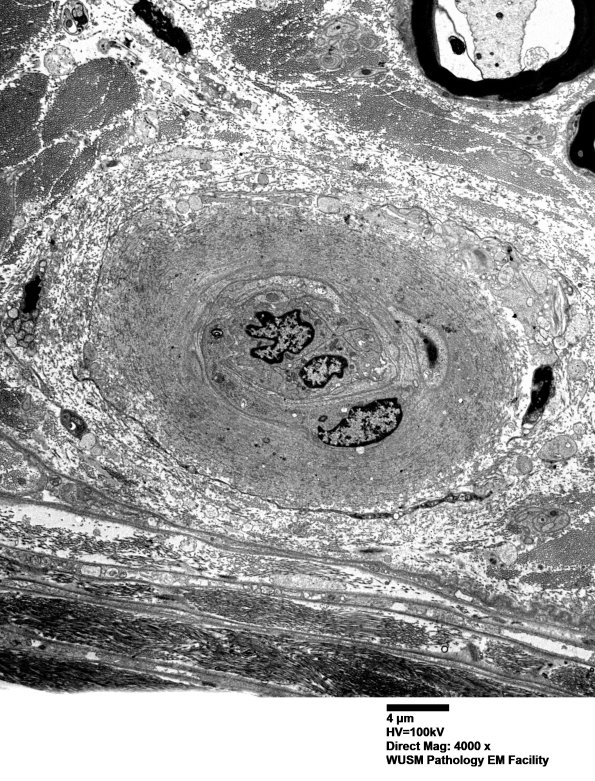

14B1A-D The endoneurial vessel shown here is expanded by collagen deposition with a small contribution by fragments of basal lamina. (electron micrographs)